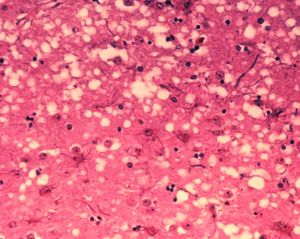

변형 프리온(PrPSc)이 체내에 유입되면, 뇌에 존재하는 정상 프리온 단백질(PrPC)을 점진적으로 변형시킨다. 변형된 프리온은 다시 다른 정상 프리온을 연쇄적으로 변형시켜 그 수가 기하급수적으로 증가하게 된다. 이렇게 증가한 변형 프리온들은 서로 뭉쳐 아밀로이드 플라크라는 단백질 덩어리를 형성하고, 이는 뇌 신경세포를 파괴하여 뇌 조직에 스펀지처럼 미세한 구멍이 뚫리는 해면상 변화를 일으킨다. 이로 인해 소는 신경계 이상 증상을 보이다가 결국 폐사한다.[15] 감염된 소는 2년에서 8년 정도의 긴 잠복기를 거친 후 증상을 나타내는 것으로 추정된다.[123][124]

현재, 신경병리학적 및 면역조직화학적 방법을 사용하여 ''사후'' 뇌 조직을 검사하는 것 외에는 변형 프리온 단백질(PrPSc)을 신뢰성 있게 감지할 수 있는 방법이 없다. 비정상적으로 접힌 PrPSc 형태의 PrP 축적은 질병의 특징이지만, 혈액이나 소변과 같이 쉽게 접근할 수 있는 체액에서는 매우 낮은 수준으로 존재한다. 연구자들은 PrPSc를 측정하는 방법을 개발하려고 시도했지만, 혈액과 같은 물질에 사용할 수 있는 방법은 아직 완전히 받아들여지지 않았다. 전통적인 진단 방법은 뇌의 숨뇌 및 기타 조직에 대한 ''사후'' 조직병리학적 검사에 의존하며, 면역조직화학은 프리온 단백질 축적을 입증하는 데 사용될 수 있다.[25]